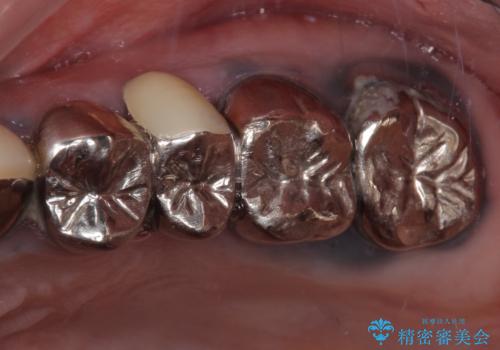

冷たいものがしみて奥歯が痛い 気になる歯並びも治した